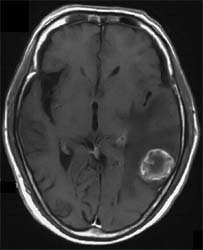

tenisei_fig_1

転移性脳腫瘍の症状に特徴的なものはなく、頭蓋内悪性脳腫瘍一般の症状である頭蓋内圧亢進症状(頭痛、嘔気、精神症状)と病巣の存在する部位の局在症状が主体です。

CT、MRIで境界明瞭な腫瘤でいわゆるリング状造影効果をしめすものが多い。